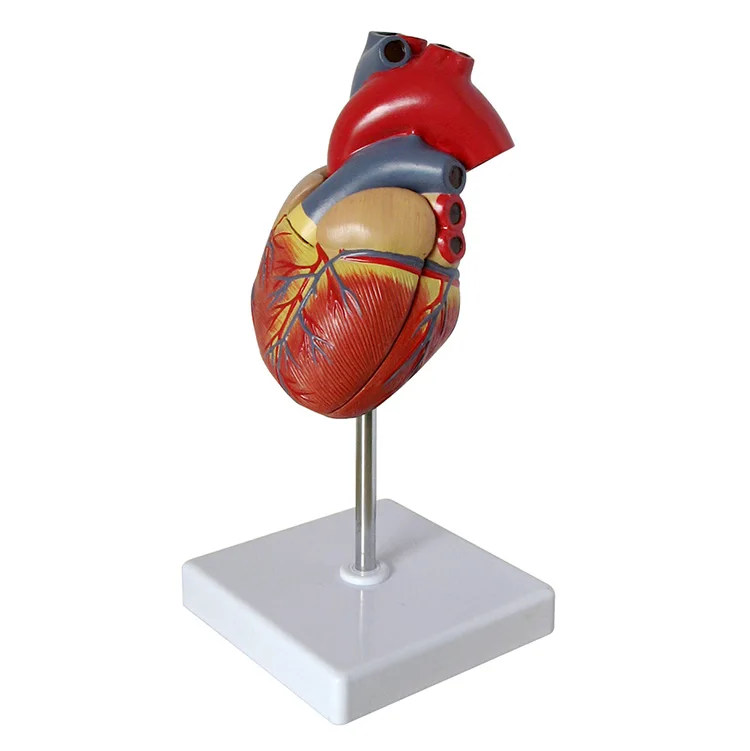

Valentine’s Day ช็อกโกแลตหัวใจ 12 ชิ้น – ของขวัญรังนกแท้ คอซซี่ โมเดลหัวใจมนุษย์ (Human Heart) | Shopee Thailand

โมเดลหัวใจมนุษย์ (Human Heart) | Shopee Thailand หัวใจมนุษย์ ภาพสต็อก – ดาวน์โหลดรูปภาพตอนนี้ – หัวใจ – อวัยวะภายใน …

ขยายกายวิภาคหัวใจมนุษย์รุ่น 3 ชิ้นส่วน – Buy กายวิภาคหัวใจ,หัวใจ … หัวใจมนุษย์ การออกแบบรายละเอียด ภาพประกอบสต็อก – ดาวน์โหลดรูปภาพตอนนี้ …

ชีวิตพลาสติกกายวิภาคหัวใจมนุษย์รุ่น2ชิ้นส่วน – Buy การสอนรุ่น,Anatomy … ช็อคโกแลตรูปหัวใจ [ภาพวาดฟรี] | OkusanPix

หัวใจวิทยาศาสตร์เรื่องกายวิภาคศาสตร์ทางการแพทย์หัวใจมนุษย์รุ่นขาย – Buy … รูปเวกเตอร์ฟรีหัวใจการ์ตูนปุ่ม PNG , หัวใจมนุษย์, หัวใจ, เซลล์ภาพ PNG …

รักสุดใจ! ช่อช็อกโกแลตให้เธอ รวมไอเดียช่อช็อกโกแลตสื่อรัก มอบให้แฟน แบบจำลองหัวใจมนุษย์ขนาดชีวิตที่มีสีพื้นโปร่งใสโรคหัวใจทางการแพทย์แบบ …

แบบจำลองหัวใจมนุษย์ขนาดชีวิตที่มีสีพื้นโปร่งใสโรคหัวใจทางการแพทย์แบบ … Chocolate Heart, Hand-drawn sketch Chocolate s, brown, food png | PNGEgg

Chocolate Heart, Hand-drawn sketch Chocolate s, brown, food png | PNGEgg แบบจำลองหัวใจมนุษย์ขนาดชีวิตที่มีสีพื้นโปร่งใสโรคหัวใจทางการแพทย์แบบ …

แบบจำลองหัวใจมนุษย์ขนาดชีวิตที่มีสีพื้นโปร่งใสโรคหัวใจทางการแพทย์แบบ … ช็อกโกแลต รูปฟุตบอล เหรียญทอง หัวใจ บรรจุ 60 ชิ้น | Shopee Thailand

In-306 3d กายวิภาคศาสตร์หัวใจมนุษย์รูปแบบทางการแพทย์พลาสติกกายวิภาค … หัวใจมนุษย์ ภาพสต็อก – ดาวน์โหลดรูปภาพตอนนี้ – หัวใจ – อวัยวะภายใน, การ …

หัวใจวิทยาศาสตร์เรื่องกายวิภาคศาสตร์ทางการแพทย์หัวใจมนุษย์รุ่นขาย – Buy … หัวใจวิทยาศาสตร์เรื่องกายวิภาคศาสตร์ทางการแพทย์หัวใจมนุษย์รุ่นขาย – Buy …

หัวใจวิทยาศาสตร์เรื่องกายวิภาคศาสตร์ทางการแพทย์หัวใจมนุษย์รุ่นขาย – Buy … Anatomy หัวใจมนุษย์รุ่นพลาสติกทางการแพทย์กายวิภาคหัวใจจัมโบ้รุ่นอวัยวะ …

Anatomy หัวใจมนุษย์รุ่นพลาสติกทางการแพทย์กายวิภาคหัวใจจัมโบ้รุ่นอวัยวะ … รูปช็อกโกแลตหัวใจพร้อมน้ำเชื่อม PNG , วาเลนไทน์วัน, หัวใจ, วันแห่งความ …

3d Anatomy หัวใจมนุษย์รุ่นพลาสติกทางการแพทย์กายวิภาคหัวใจจัมโบ้รุ่น … หัวใจวิทยาศาสตร์เรื่องกายวิภาคศาสตร์ทางการแพทย์หัวใจมนุษย์รุ่นขาย – Buy …

หัวใจวิทยาศาสตร์เรื่องกายวิภาคศาสตร์ทางการแพทย์หัวใจมนุษย์รุ่นขาย – Buy … ส่งไว🚀24ชม. เจบีช็อกโกแลต รูปฟุตบอล เหรียญทอง เหรียญเงิน ทองแท่ง หัวใจ …

ส่งไว🚀24ชม. เจบีช็อกโกแลต รูปฟุตบอล เหรียญทอง เหรียญเงิน ทองแท่ง หัวใจ … Anatomy หัวใจมนุษย์รุ่นพลาสติกทางการแพทย์กายวิภาคหัวใจจัมโบ้รุ่นอวัยวะ …

Anatomy หัวใจมนุษย์รุ่นพลาสติกทางการแพทย์กายวิภาคหัวใจจัมโบ้รุ่นอวัยวะ … ภาพประกอบแบนเวกเตอร์หัวใจมนุษย์ขนาดใหญ่บนพื้นหลังสีขาว ภาพประกอบสต็อก …

หัวใจมนุษย์กายวิภาครุ่นวิทยาศาสตร์การแพทย์รูปแบบการสอน ห้องหัวใจมนุษย์: คำอธิบายโครงสร้างหน้าที่และประเภท

หุ่นจำลองหัวใจมนุษย์ 3d มนุษย์กายวิภาครุ่นหัวใจมนุษย์สำหรับซัพพลายเออร์แบบครบวงจรวิทยาศาสตร์ …

3d มนุษย์กายวิภาครุ่นหัวใจมนุษย์สำหรับซัพพลายเออร์แบบครบวงจรวิทยาศาสตร์ … 3d Anatomy หัวใจมนุษย์รุ่นพลาสติกทางการแพทย์กายวิภาคหัวใจจัมโบ้รุ่น …

3d Anatomy หัวใจมนุษย์รุ่นพลาสติกทางการแพทย์กายวิภาคหัวใจจัมโบ้รุ่น … อวัยวะหัวใจของมนุษย์ | องค์ประกอบกราฟฟิก แบบ PSD ดาวน์โหลดฟรี – Pikbest

หัวใจมนุษย์กายวิภาครุ่นวิทยาศาสตร์การแพทย์รูปแบบการสอน 15 Porch ช็อกโกแลต Fudge แม่พิมพ์ซิลิโคนหัวใจรูปเค้กช็อกโกแลตตกแต่ง DIY …

อุปกรณ์การศึกษากายวิภาคศาสตร์รุ่นหัวใจมนุษย์รุ่นสำหรับโรงเรียนขนาดชีวิต … วิธีทำ “นามะช็อกโกแลต” ของฝากยอดฮิตจากญี่ปุ่น อร่อยหรูดูแพง แต่ทำง่าย …

In-306 3d กายวิภาคศาสตร์หัวใจมนุษย์รูปแบบทางการแพทย์พลาสติกกายวิภาค … บอลลูนหัวใจมนุษย์ Angioplasty เวกเตอร์ ภาพประกอบ ภาพประกอบสต็อก – ดาวน์ …

โรงงานโดยตรงขาย Anatomy หัวใจมนุษย์การฝึกอบรมชุดอวัยวะภายในรุ่น – Buy …